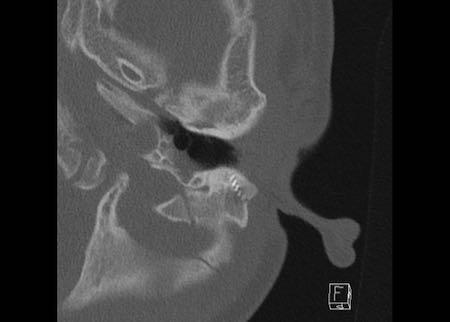

Bên trái là hình ảnh của một bé trai 2 tuổi với teo ống tai ngoài xương hai bên.

Xương búa và xương đe hợp nhất (mũi tên).

Ốc tai bình thường.